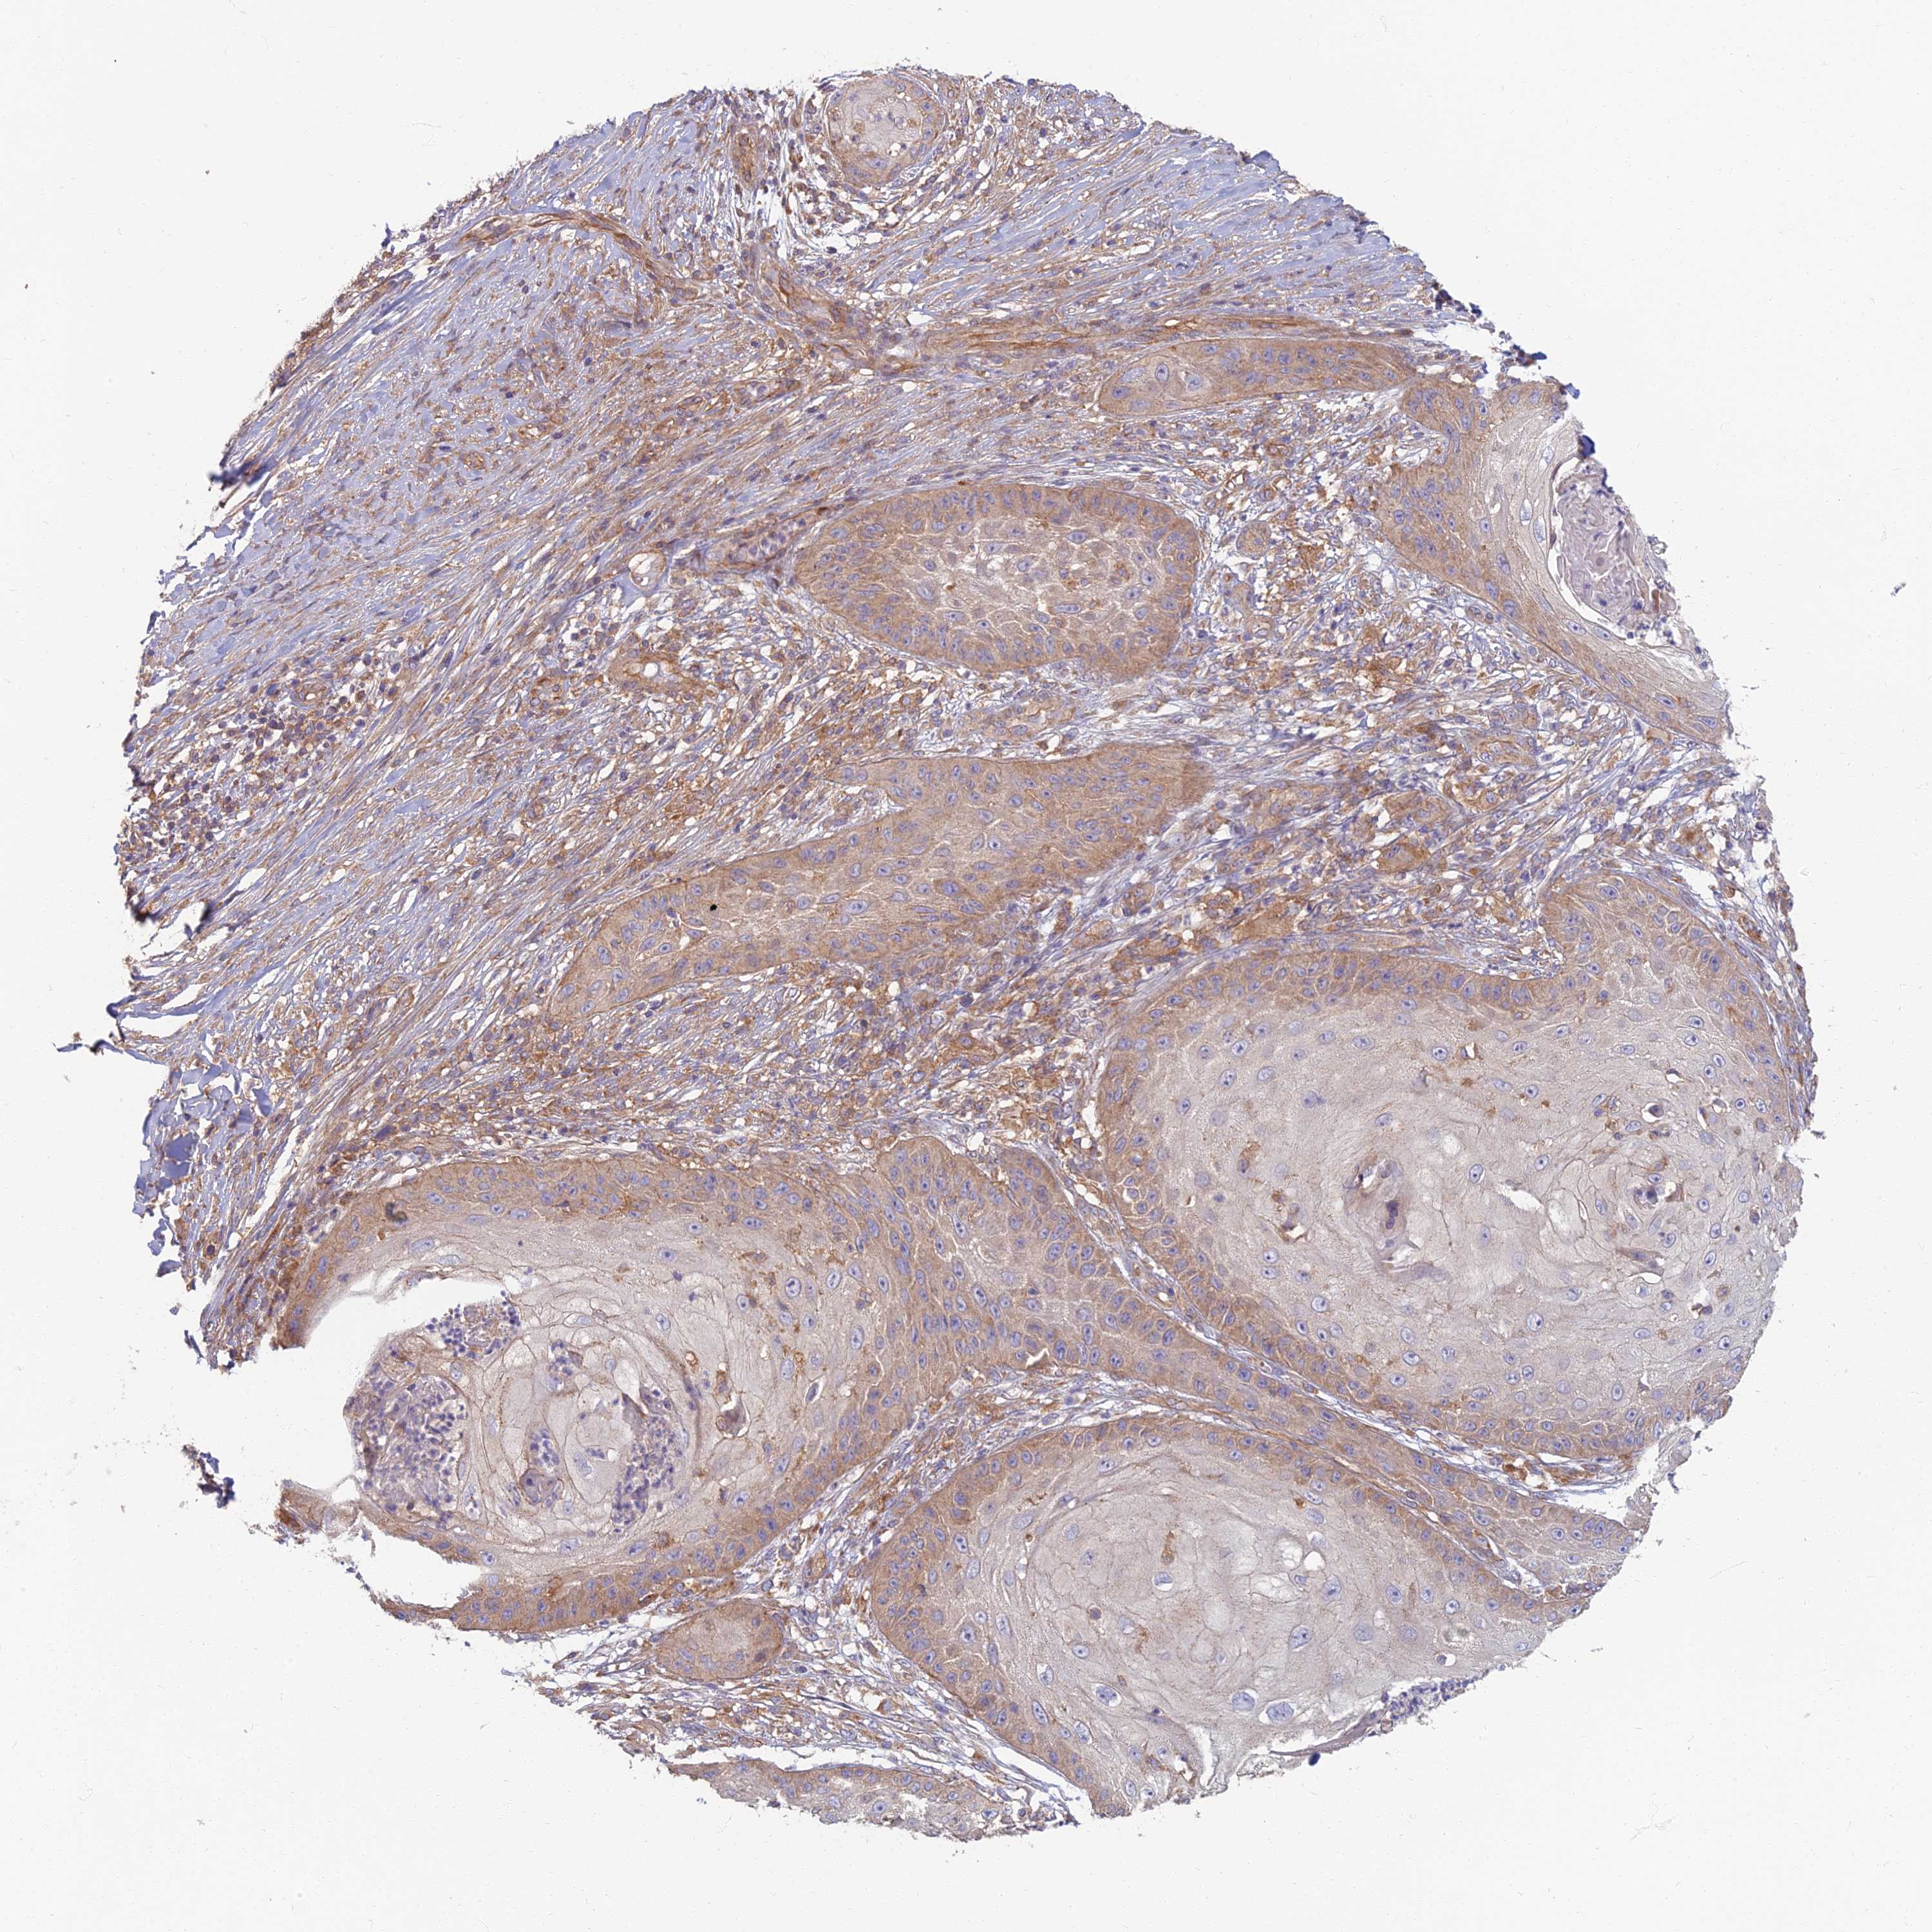

SKIN CANCER - Protein expressioni

A mouse-over function shows sample information and annotation data. Click on an image to view it in a full screen mode. Samples can be filtered based on level of antibody staining by selecting one or several of the following categories: high, medium, low and not detected. The assay and annotation is described here.

Antibody stainingi

Antibody staining in the annotated cell types in the current human tissue is reported as not detected, low, medium, or high, based on conventional immunohistochemistry profiling in selected tissues. This score is based on the combination of the staining intensity and fraction of stained cells.

Each image is clickable and will lead to virtual microscopy that enables deeper exploration of all samples and also displays staining intensity scores, fraction scores and subcellular localization as well as patient and tissue information for each sample.

Antibody HPA044878

Staining

High

Medium

Low

Not detected

Intensity

Strong

Moderate

Weak

Negative

Quantity

>75%

75%-25%

<25%

None

Location

Nuclear

Cytoplasmic/membranous

Cytoplasmic/membranous,nuclear

Squamous cell carcinoma, NOS